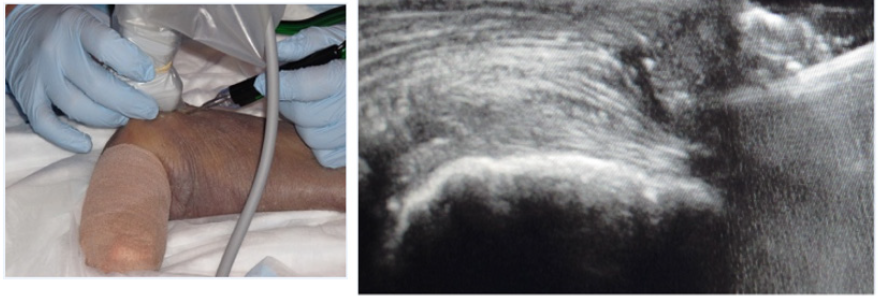

Since its origins in the sixteenth century, surgical education using cadavers remains the most realistic simulation method [1]. Cadavers expose trainees to real anatomy and variations that can be encountered in patients (Figure 3A & 3B). The ability to handle soft tissue and experience planes of dissection is something that no other simulation except for animal models can provide. However, the degree of fidelity depends on the condition of the cadaver (fresh versus embalmed, age of death, etc.) and the simulation design [72]. In support of this belief, Camp et al. [73] found that residents trained in diagnostic knee arthroscopy on a cadaver performed better than those who trained using a VR simulator, indicating disparity between the two simulations. Cadavers, however, have high costs associated with acquiring, preparing, and storing the specimens, making repetition impractical [21]. There is also the risk of disease transmission with fresh cadavers, as well as the disproportionate representation of the elderly population whose bone composition may differ from the general orthopedic patient population.

Figure 3: (A) Cadaver based training of an ultrasound guided percutaneous tennis elbow debridement. (B) Ultrasound image of the surgical probe within the extensor mass of the elbow.